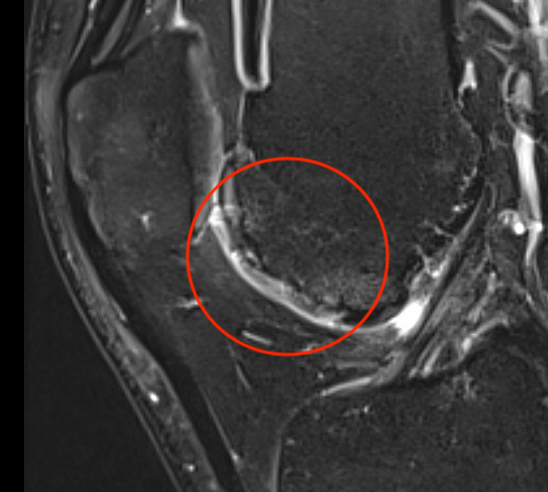

MRI

AMIC procedure of a full thickness patella lesion